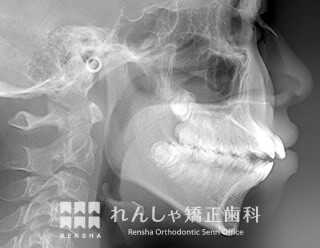

上顎前突(18歳 治療期間:2年10か月)

上前歯をできるだけ内側に移動させたい場合は、抜歯するだけでなく上奥歯を後方へ移動します。

上前歯を大きく後方に移動することができれば、口元を大きく変化させることができます。

| 主訴 | 上前歯の前突 |

|---|---|

| 診断名 | Angle Class II 上顎前突 |

| 初診時年齢 | 16歳2か月 |

| 装置名 | マルチブラケット装置 |

| 抜歯非抜歯 | 上下顎左右第一小臼歯の抜歯(合計4本) |

| 治療期間 | 2年10か月 |

| 費用の目安 | 約88万円+消費税(検査料金、都度の処置費用等も合わせた総額) |

| リスク副作用 | 歯の移動に伴う軽微な歯根吸収、歯槽骨吸収、歯肉退縮(いずれも本症例ではほぼ無し)、矯正器具装着中のカリエスリスク増大(本症例ではカリエス発生無し) |